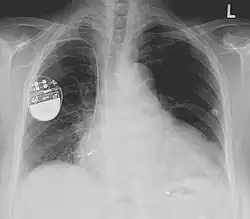

Radiographie d'un thorax cachant un stimulateur cardiaque.

Une radiographie pulmonaire est faite de manière usuelle, après l'intervention, afin de vérifier l'absence de pneumothorax (accident possible en cas de ponction de la veine sous-clavière) et le positionnement des sondes[14].